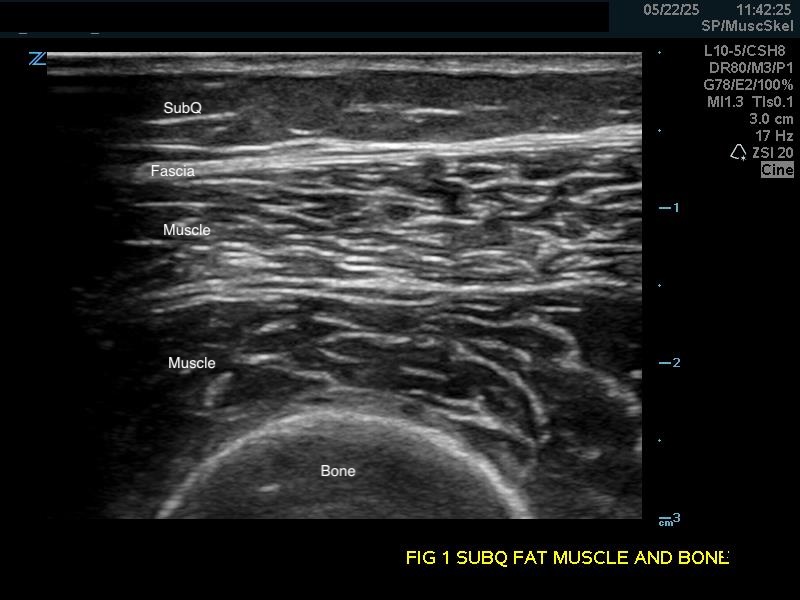

Bones

Bright hyperechoic lines with no echoes deep to the densely calcified cortex. Ultrasound can only view the surface of bones.

Figure 1a.

(A) Longitudinal view. Bone appears as a distinct bright echogenic line with no visible structures beneath, Subcutaneous fat appears relatively hypoechoic with thin septations of connective tissue.

Soft Tissue

Subcutaneous fat: Relatively hypoechoic with thin septations of connective tissue. The thickness of this layer varies and may require increasing the depth setting of your machine.

Longitudinal view. Bone appears as a distinct bright echogenic line with no visible structures beneath, Subcutaneous fat appears relatively hypoechoic with thin septations of connective tissue.

Muscle: Longitudinally, appears as slabs of striated hypoechoic tissue contained within the thin hyperechoic lines of fascia. Viewed transversely, muscle striations or septa appear dotted and punctate or form short lines. Fascial lines separate muscle compartments.